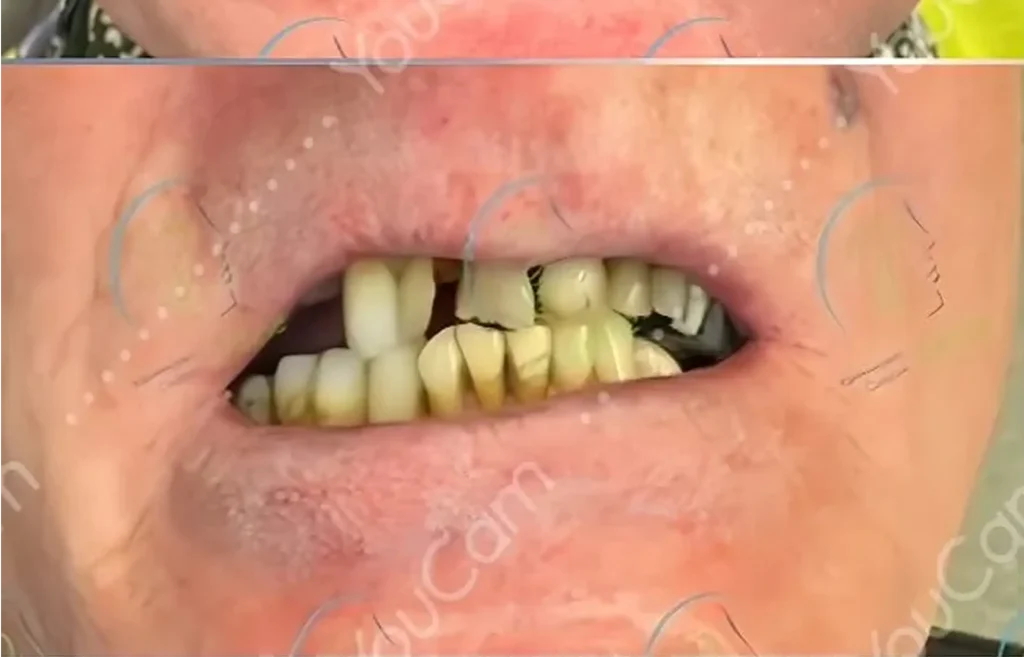

Tandimplantat – En säker och effektiv behandling för att ersätta förlorade tänder Att förlora en eller flera tänder kan få både funktionella och estetiska konsekvenser. Det kan påverka tuggförmågan, talet och självförtroendet – samtidigt som det kan leda till förändringar i käkbenet och ansiktsstrukturen över tid. I dagens moderna tandvård är tandimplantat en av de mest […]